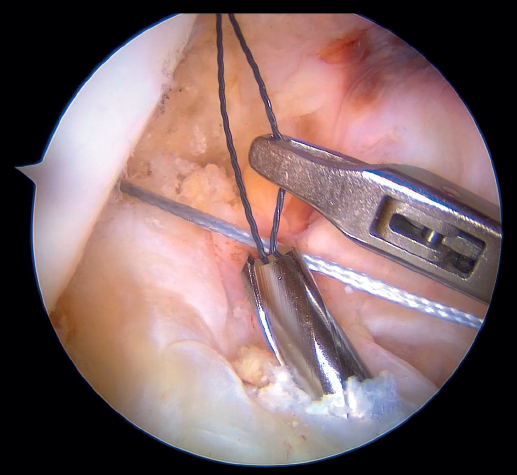

Outside the knee, the threads are loaded into a knotless anchor implant with a tape that will act as anterior reinforcement of the ACL when attached to the tibia. Once the implant has been loaded, it is inserted into the previously prepared site. This step is facilitated when viewing is made from the anteromedial portal, as it affords a better perspective of the zone (Figure 5). Once the implant has been inserted, the suture threads are cut at the level of the condylar wall.